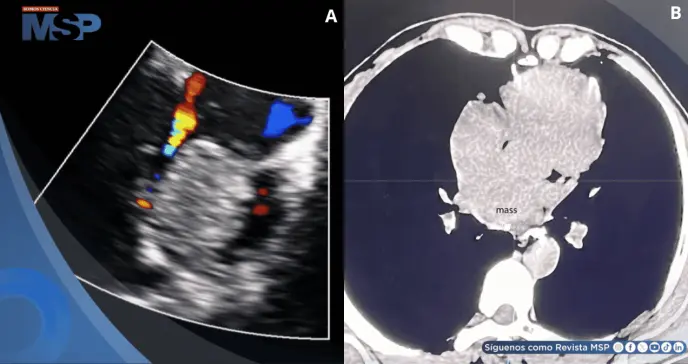

Se le realizó una ecografía cardíaca con color que reveló una masa de eco débil en la cavidad izquierda, sugiriendo un mixoma (tumor cardíaco benigno). En más estudios realizados en un centro de atención terciaria, se encontró hipoecogenicidad y dilatación en la aurícula izquierda, disminución de la distensibilidad del ventrículo izquierdo, insuficiencia aórtica leve y dilatación de la aorta y las arterias pulmonares.

En el último ingreso se le realizó un electrocardiograma que mostró un ritmo sinusal, taquicardia nodal no paroxística y desconexión auriculoventricular incompleta. La ecocardiografía transtorácica reveló una masa ecogénica anómala de 5 cm × 4 cm en la aurícula izquierda, adherida a la parte media del tabique auricular.